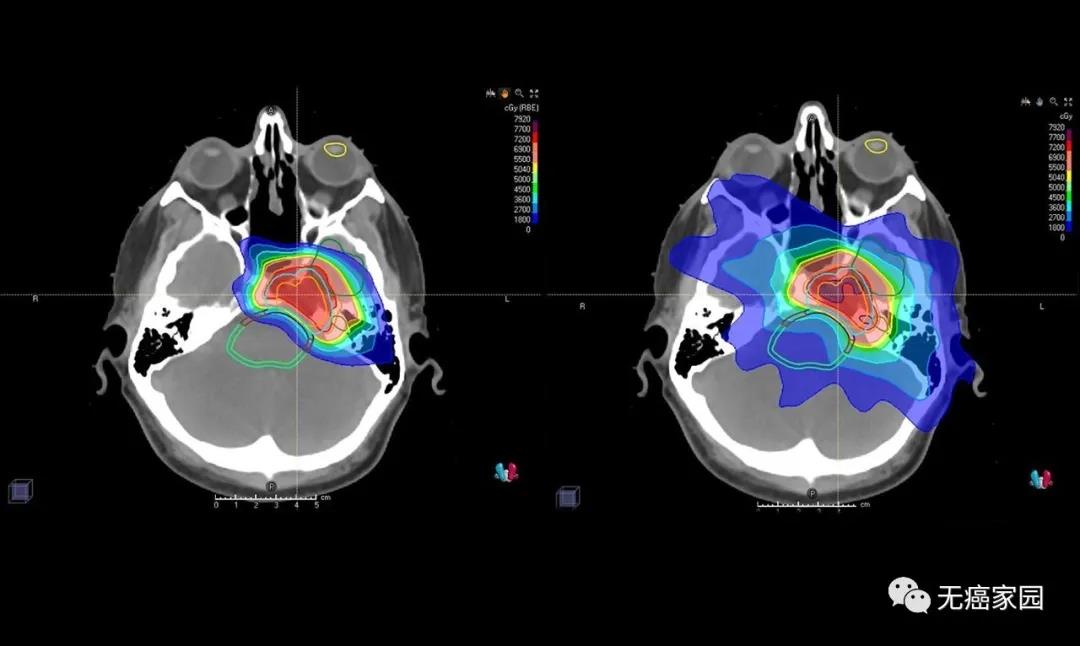

近期,约翰·霍普金斯·金梅尔癌症中心的权威质子中心医学主任,医学博士Christina Tsien在其官方平台上表示,质子疗法能够提供针对脑瘤和脊髓肿瘤的靶向治疗...